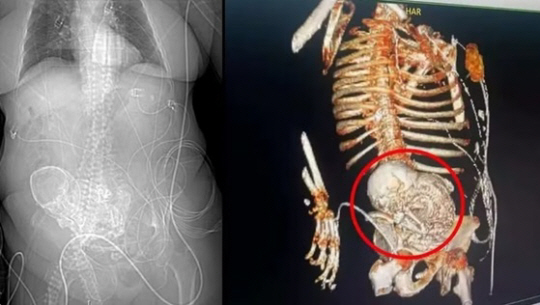

브라질의 한 할머니가 심한 복통으로 병원을 찾았다가 뱃속에서 50여 년 전에 죽은 태아를 발견했다. 할머니는 긴급 수술을 받았지만 숨졌다.

19일(현지 시간) 브라질 언론매체 G1에 따르면 마투그로수두수우에 사는 올해 81세 할머니는 지난 14일 요로감염 증상과 복통으로 지역 병원을 찾았다. 의료진은 컴퓨터단층촬영(CT) 결과 이 할머니의 뱃속에서 석회처럼 된 태아(석태아)를 확인했다고 한다.

적출 수술을 진행했던 병원 측은 ‘마지막 임신이 56년 전’이라는 환자 생전 언급과 석태아 상태 등을 토대로, 아이가 50여 년 전에 사망한 것으로 추정했다.